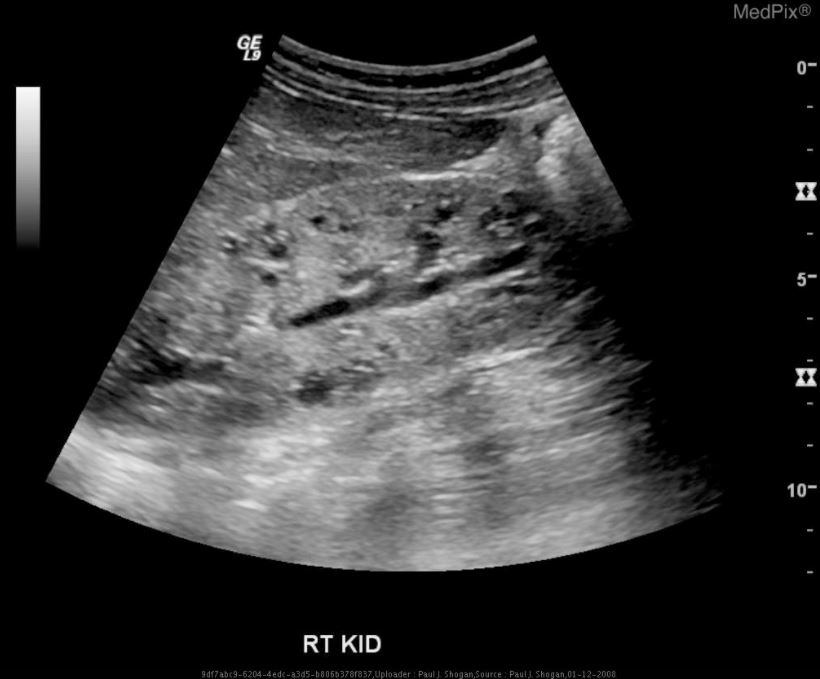

La enfermedad renal poliquística autosómica dominante (ADPKD), la enfermedad renal poliquística autosómica recesiva (ARPKD) y el riñón displásico multicístico presentan características distintivas en la ecografía neonatal.

3. Riñón displásico multicístico:

Esta condición se caracteriza por la presencia de múltiples quistes grandes que reemplazan el parénquima renal normal, resultando en una pérdida de la arquitectura renal normal. A diferencia de las enfermedades poliquísticas, el riñón displásico multicístico generalmente afecta solo un riñón y no presenta una diferenciación corticomedular.[1]

La ecografía es una herramienta crucial para diferenciar estas condiciones en neonatos, permitiendo una evaluación detallada de la estructura y la ecogenicidad renal, así como la identificación de quistes y su distribución.